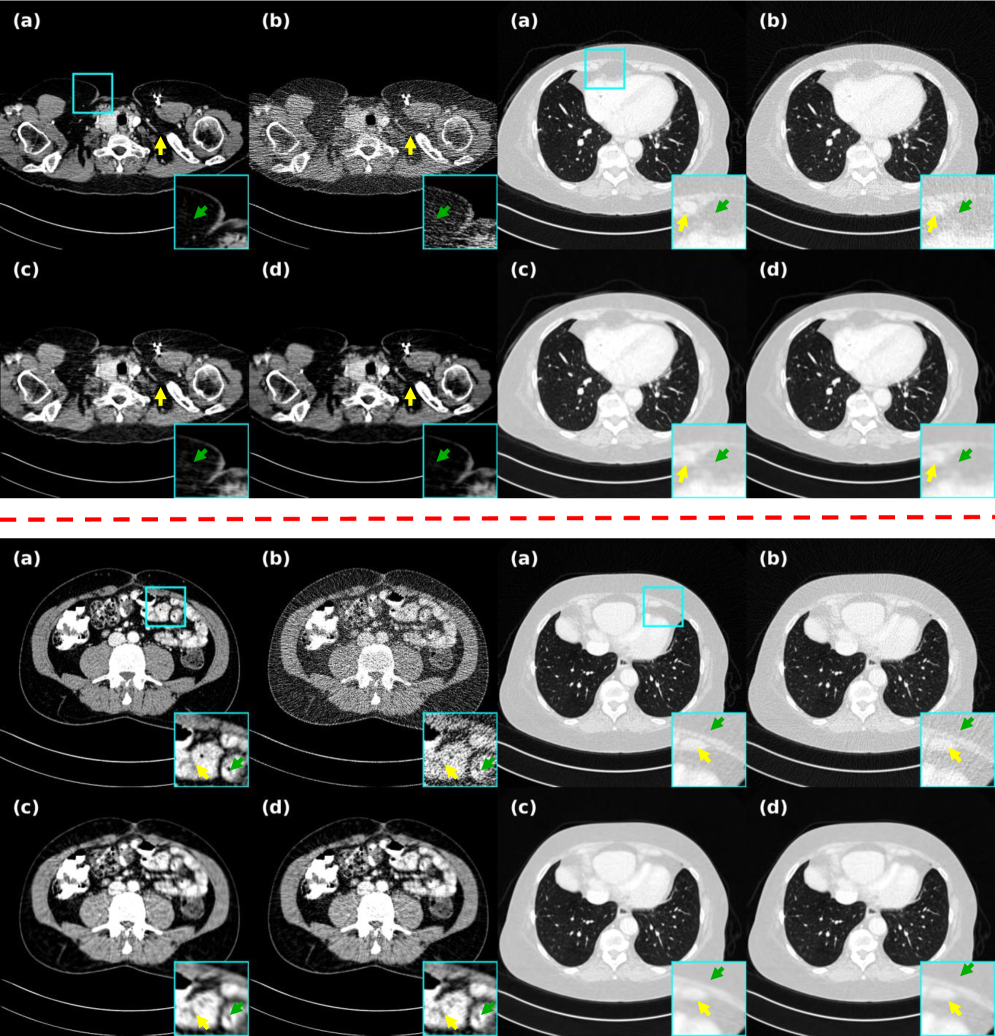

4.4.3 Representation of real clinical data and mouse PCCT data

To better demonstrate the scalability of generalization of EGenDiff, validation was conducted using both mouse and real clinical data. As demonstrated in Fig. 10, our method outperforms AdaReNet in detail recovery and noise suppression. It effectively removes noise around lesions while preserving diagnostic features—capabilities crucial for clinical practice. IPDM exhibits smoothing and detail loss after dual-domain processing, while Noise2Sim obscures structurally important regions. Though other methods surpass FBP, they show limited adaptability to real noise patterns. On the contrary, EGenDiff removes the noise to a large extent and the pathological features are well reconstructed. Meanwhile, the material decomposition results of mouse spectral CT shown in Fig. 11 also indicate that EGenDiff can be extended to different fields and achieve the best results. It will bring a new paradigm to self-supervised denoising methods.

4.5 Ablation Study

4.5.1 Validity of the dual domain strategy

This study first presents a holistic analysis of the proposed framework and performs ablation studies on single projection and overall stages. As shown in Fig. 12 and Table 3, denoising solely in the projection domain reveals inadequate noise suppression, incomplete recovery of muscle tissue details, and suboptimal restoration of skeletal structures. These limitations are effectively addressed through subsequent knowledge distillation in the image domain, demonstrating that the initial reconstruction and original data serve as complementary guidance, compensating for each other’s limitations during the reconstruction process.

4.5.2 Importance of self-enhancing similarity in projection domain

After analyzing the effectiveness of the dual-domain phase, we focus on the proposed self-enhancing similarity strategy in the projection domain phase. This strategy is proposed to shorten the dissimilarity between contextual sub-data. So it focuses on highlighting the loss weight of similarity and ignoring the excessive part of dissimilarity. As shown in Fig. 12 and Table 3, implementations without this strategy exhibit feature smoothing and gradient disappearance, impairing the subsequent image-domain refinement stage’s ability to discriminate between noise and tissue structures, ultimately leading to suboptimal performance.

4.5.3 Pixel-level self-correcting validity and difference from fixed weights

Subsequently, we carried out the difference between self-correction at the pixel level of the inference process and taking fixed weights. Fig. 13 and Table 3 add fully illustrate the situation, with fixed weights we selected as , and even selected as , even though this is not in line with the original intent of the dual-stage. As can be seen, our pixel-level fusion can make a balance between and for each pixel, laying the groundwork for entering into image inference, and showing competitive results in both metrics and reconstruction.